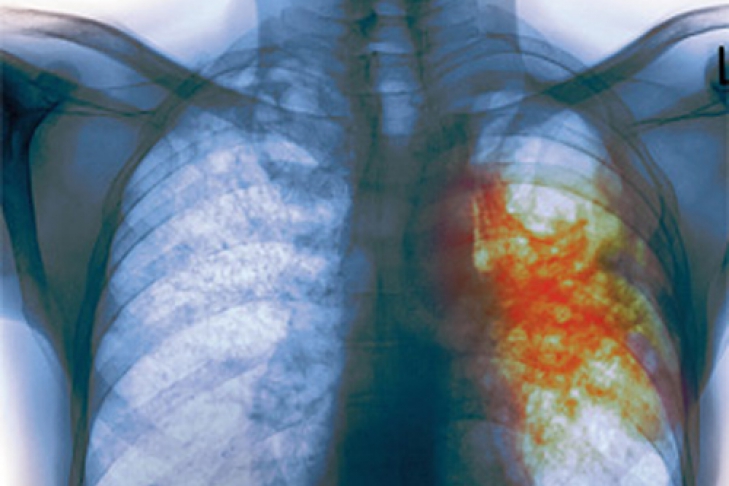

Украинцев косит туберкулез

Страна находится на первом месте по смертности от заболевания в Европе

По данным Коалиции организаций «Остановим туберкулез вместе», сейчас Украина занимает первое место среди стран Европы по смертности от туберкулеза, а также второе - по заболеваемости. Об этом на брифинге в Киеве заявил сопредседатель Коалиции организаций «Остановим туберкулез вместе» Сергей Борткевич. Эксперт считает, что официальная статистика, по которой за 2009 год количество больных туберкулезом сократилось на 2%, не свидетельствует о том, что ситуация стабилизируется.

«Есть данные статистики, что за 2009 год количество больных туберкулезом сократилось на 2%, однако, это не следствие выздоровления, а результат высокой смертности среди инфицированных туберкулезом», - заявил он.